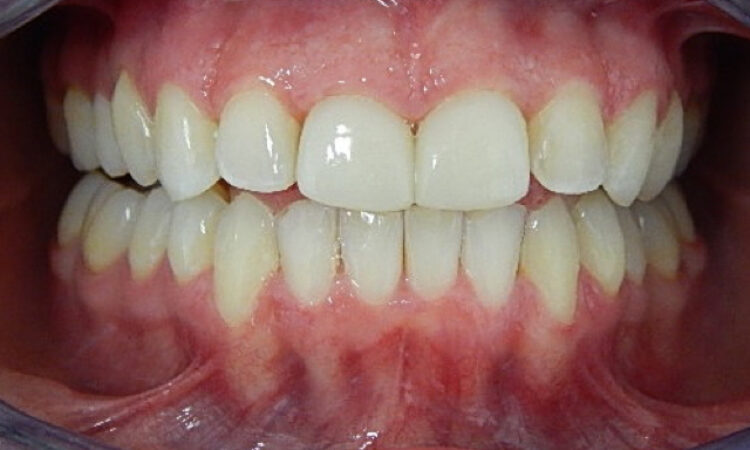

Before - puredental After - puredental

Case 20 - Invisalign®